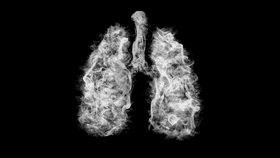

Health officials in the State of Illinois are investigating the death of an individual who used a vape and was later hospitalized with severe respiratory illness.

The rest of this article is behind a paywall. Please sign in or subscribe to access the full content.It comes after the Centers for Disease Control and Prevention (CDC) launched an investigation earlier this month following reports of a mysterious lung disease affecting almost 100 people this summer across more than a dozen US states. No further information has been provided about the individual who has died, other than that they were an adult living in Illinois.

“The severity of illness people are experiencing is alarming and we must get the word out that using e-cigarettes and vaping can be dangerous,” said Illinois Department of Public Health (IDHP) Director Ngozi Ezike in a statement. “We requested a team from the Centers for Disease Control and Prevention to help us investigate these cases and they arrived in Illinois on Tuesday.”

The reported number of people suffering from respiratory issues who have used e-cigarettes or vaped has doubled in just one week, with a total of 22 people between the ages of 17 and 38 years old having been hospitalized. State and federal health officials, along with the US Food and Drug Administration, say that they are now investigating the names and types of products and devices used, as well as where they were purchased. No specific product has been identified, though many patients report having used tetrahydrocannabinol (THC)-containing products. However, it is not clear if these cases have a common cause or if they are different diseases with similar symptoms.

E-cigarettes and vapes work by producing an aerosol by heating a liquid that contains nicotine, marijuana, or other drug products as well as added chemicals and flavorings which can contain harmful products like heavy metals, cancer-causing chemicals, and other volatile organic compounds. The CDC notes that e-cigarettes have the potential to benefit some people, like those aiming to quit smoking, but may harm others. Scientists are still studying the products to understand risks and possible benefits, but advise that they should never be used by youth, young adults, or pregnant women.

Experts advise that if you experience any type of chest pain or difficulty breathing in the weeks following the use of e-cigarettes or vaping products, seek immediate medical attention. Additionally, medical professionals should be aware of their patients’ recent history of using such products.